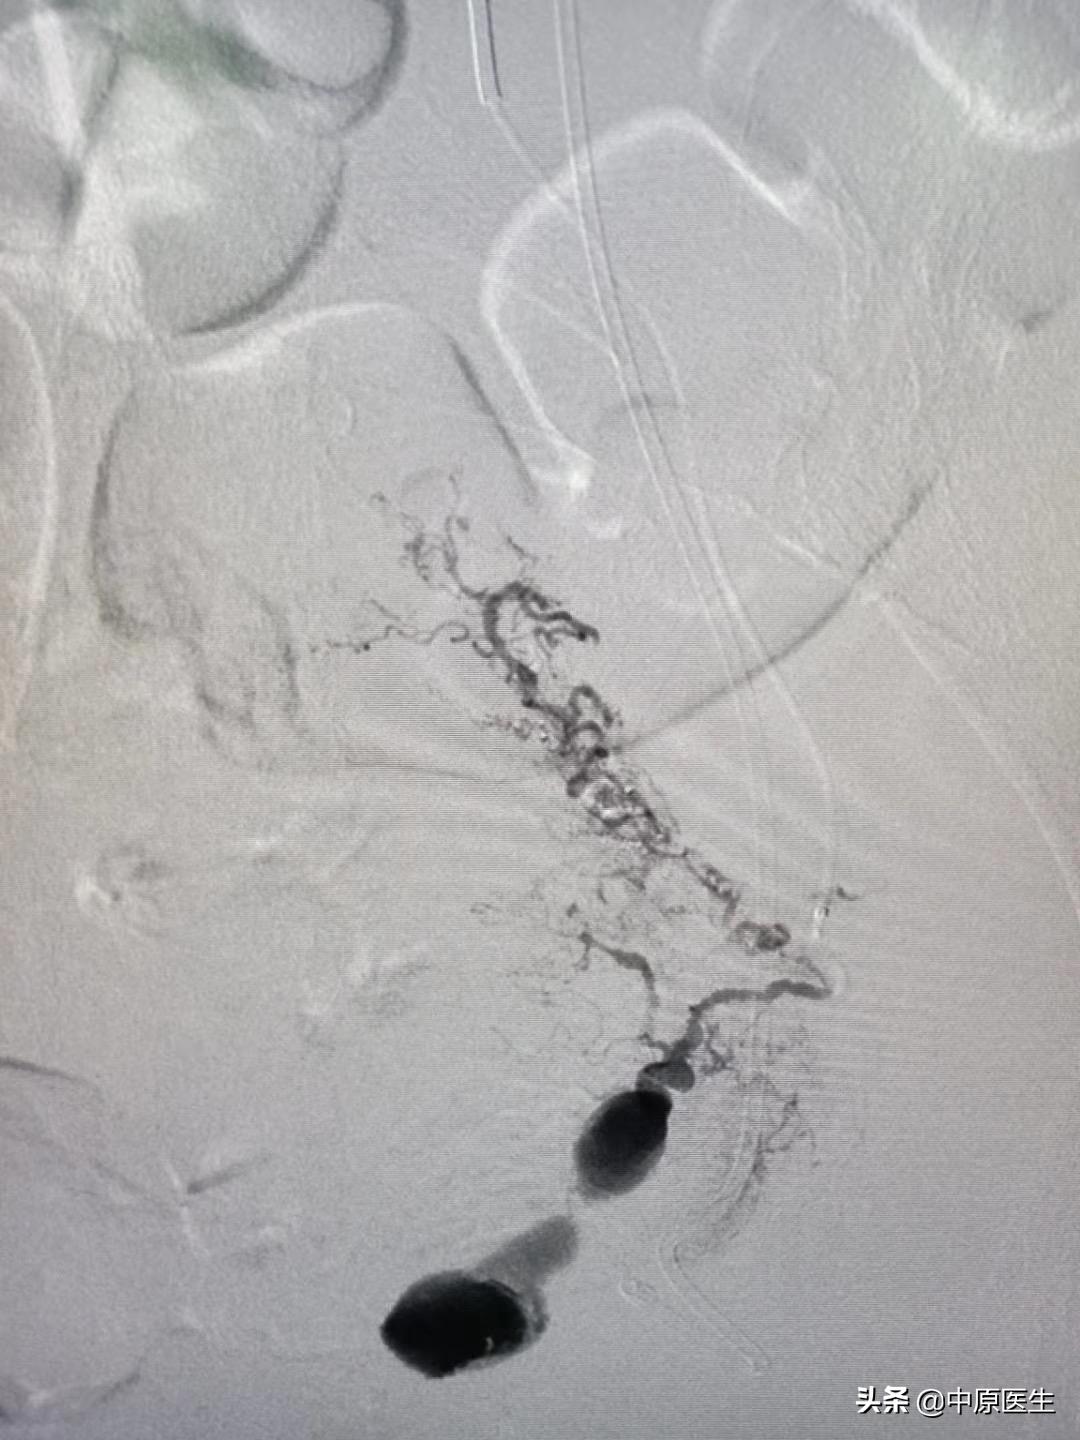

我处理好门诊事宜,十点赶往导管室,按标准预防做好术前防护、术前准备工作。在导管室的护士、技师等积极配合下,手术顺利开展,造影显示左侧子宫动脉近宫颈处有一破口、形成假性动脉瘤,假性动脉瘤破溃,造影剂快速流入宫腔内(相当于找到了河流的决口处);紧急用生物胶栓塞该破口及其远、近端血管(相当于堵住了决口及其上下游,上游流不进来、下游的倒灌不了),复查造影未见造影剂外渗、动脉瘤、静脉早显等异常血管影(成功止血)。然后选择双侧髂内动脉各分支造影未见明显异常血管,再予右侧子宫动脉栓塞。半小时顺利完成手术,病人生命体征平稳。安全送回病房,继续药物治疗。

子宫动脉栓塞术是治疗妇产科疾病常用技术,美国前国务卿赖斯曾因子宫肌瘤行子宫动脉栓塞术。具体操作是在DSA等影像设备引导下,局部麻醉,从大腿根部的股动脉穿刺、约一米粒大小的针眼,送入直径约2mm的导管到达病灶供血动脉,利用栓塞颗粒、微弹簧圈、生物胶等栓塞材料阻断病变的供血血管,达到止血和/或使病变缺少营养,继而坏死、萎缩缩小。DSA的火眼金睛可使出血动脉和肿瘤供血动脉无处可逃,这样的栓塞治疗,具有疗效确切、创伤小、无切口、恢复快、复发率低、可保留子宫的优点,这样的治疗,可以让女人保留原装子宫、做完美的女人!(本号总顾问梁宝松教授,1984年毕业于河南医科大学本科,河南省人民医院消化内科主任医师 教授)